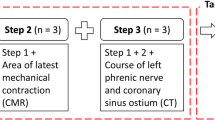

One hundred eight consecutive patients who underwent Micra™ implantation intended in the mid-septum were enrolled and randomized (3:1) into the radiography group (n = 81) with assistance of right ventriculography to illustrate the RV septum and the non-radiography group (n = 27). All subjects underwent a postoperative computed tomography (CT) scan to determine the Micra™ location. The Micra™ location assessed by CT image was compared between the two groups to confirm the accuracy of the intended pacing site. The duration of the procedure, X-ray radiation dose, and time were also compared between the two groups.

A total of 108 consecutive patients who met class I or IIa indications for pacemaker therapy and intended to receive Micra™ implantation in the RV mid-septum were prospectively enrolled from December 18, 2019 to June 17, 2021. All patients were randomized to the radiography group (N = 81) or the non-radiography group (N = 27) in a 3:1 format. The 3:1 randomization was used for allowing more patients to receive mid-septal pacing. The exclusion criteria were as follows: (1) presence of thrombosis or cancer embolus in the inferior vena cava (IVC) or portal vein; (2) presence of bilateral femoral vein stenosis or tortuosity that could cause failure to accommodate the Micra™; (3) inability to tolerate heparinization or allergy to heparin; (4) presence of implanted devices that interfered with the Micra™, such as IVC filters or tricuspid mechanical valve replacement; (5) presence of severe renal insufficiency (glomerular filtration rate < 30 mL/min) or iodine allergy; (6) acute phase of myocardial infarction; and (7) contraindications for CT scan or contrast agents. All patients signed an informed consent form prior to the surgical procedure. This study was approved by the Ethics Committee of the First Affiliated Hospital of Xinjiang Medical University (ethical approval number: K201912-10) and registered in China Clinical Trial Registry (ChiCTR2100051374). The data that support the findings of this study are available from the corresponding author on reasonable request.